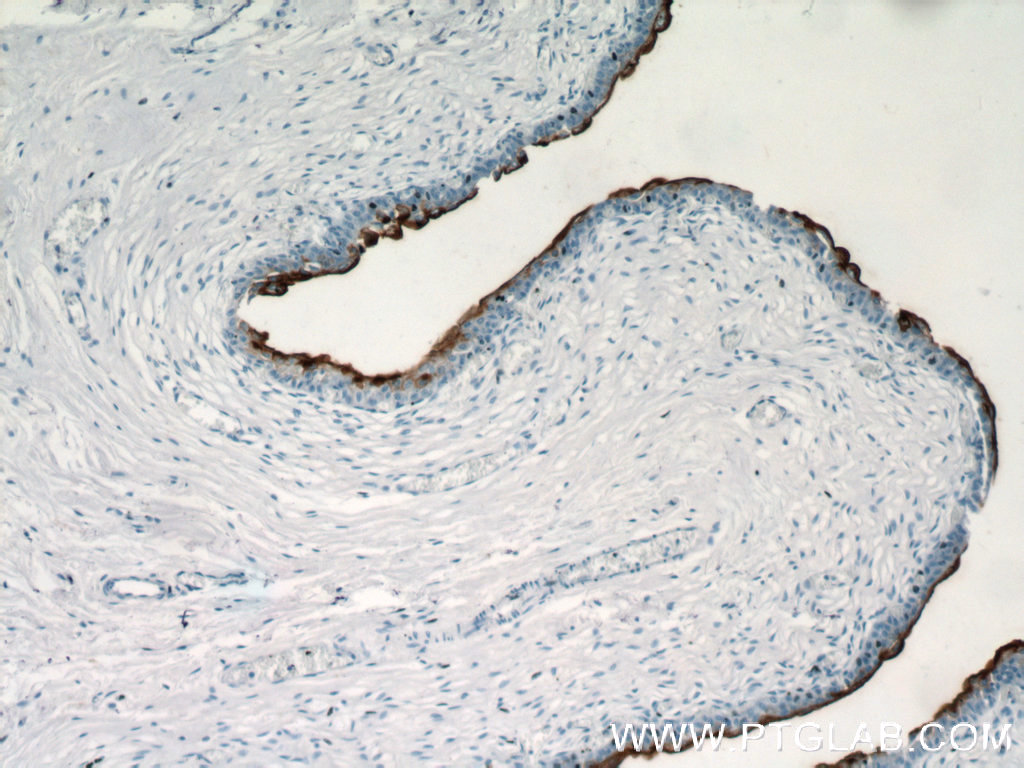

使用范围: WB,ELISA,IHC-P,IHC-F,IF

UPK3B抗体Applications